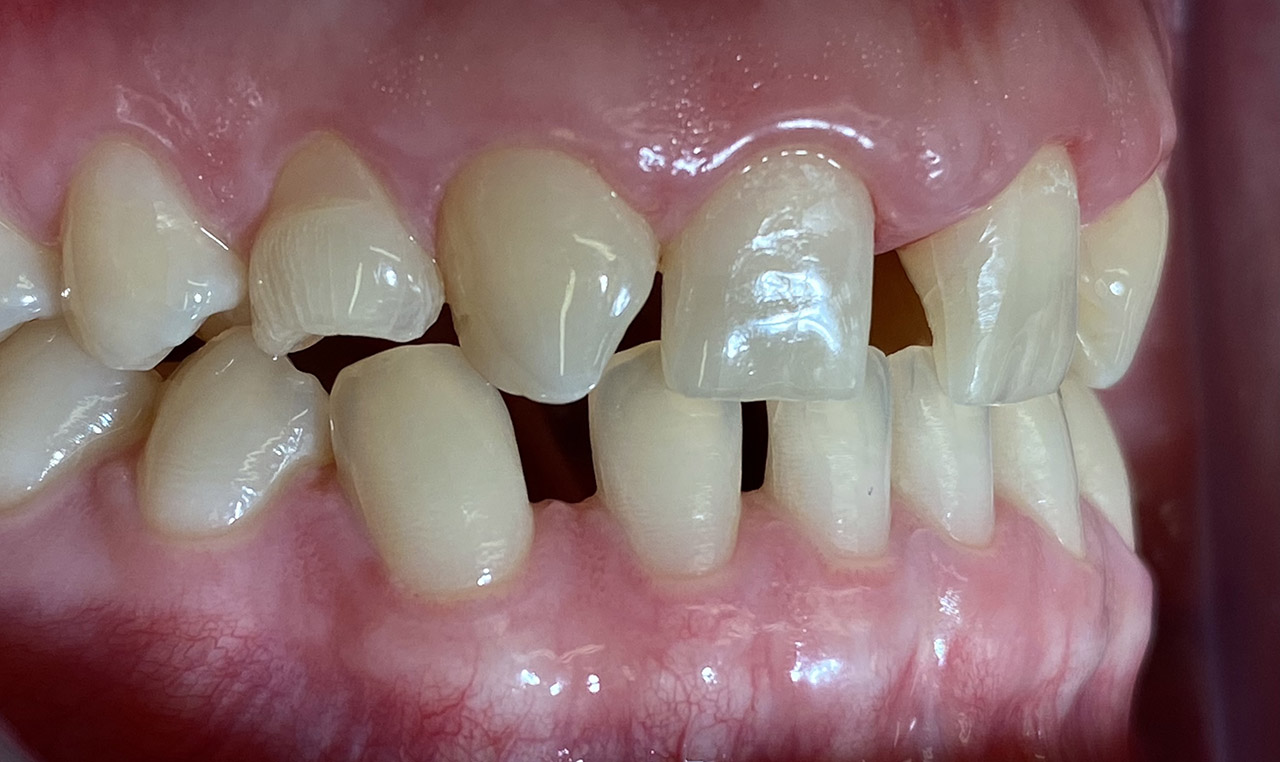

Klebebrücken bei Zahnaplasie (Nichtanlage):

Vorbehandlung (Dr. Ernst Köle): Kieferorthopädischer ”Platzhalter mit provisorischem Zahn”.

Minimalinvasive Therapie: 2 keramikverblendete Klebebrücken (“Zirkonflügerl") adhäsiv zementiert.

Konservativ ohne Knochenaufbau und Schleimhauttransplantat.